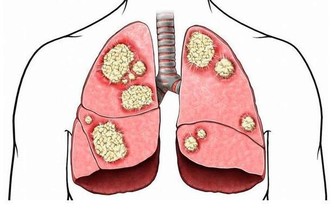

根據國健署調查,18歲以上糖尿病盛行率約為11.8%,截至今年糖尿病患人數已突破227萬人,

更高居十大死因第5名,在台灣每5名糖尿病患者就有1人死於心血管疾病,

是糖尿病患所有併發症中,發生率最高的疾病。

蔡世澤說,高油、高鈉是增加心血管疾病重要因素,過多油脂會造成血管堵塞,

超標的鈉則會導致血壓飆高以及血管彈性疲乏、硬化,增加心血管疾病發生,